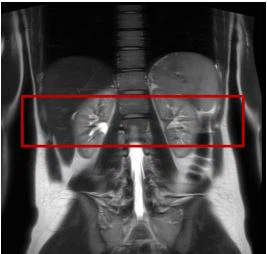

Tiedonkeruu suoritettiin 3 T skannerilla (Magnetom Prisma, Siemens AG, Healthineers, Erlangen, Saksa) käyttämällä 32-kanavaista selkärankakelaa yhdessä 30-kanavaisen runkokäämin kanssa. Anatomisten kuvien saamiseksi käytettiin puoli-Fourier-single-shot turbo-spin-echo (HASTE) -sekvenssiä kaikilla kolmella kuvan akselilla (aksiaalinen, koronaaalinen ja sagitaalinen). Näitä anatomisia kuvia käytettiin FOV-sijoitteluun seuraavassa QSM:ssä (kvantitatiivinen herkkyyskartoitus) järjestys. FOV sijoitettiin keskellemunuaiset(Kuva 1).

Kuva 1 Esimerkki FOV-sijoittelustamunuaistenQSM:n hankinta. FOV sijoitettiin keskeiseen paikkaanmunuaisetvarmistaaksesi yhtenäiset kuvausolosuhteet